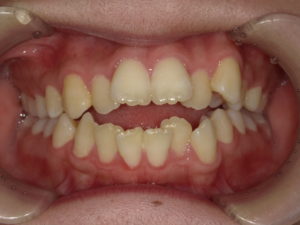

【悪い歯並び3】開咬(かいこう)

user comment….

開咬(かいこう)とは、歯を噛み合わせた際に、前歯が噛み合っていない状態を指します。「オープンバイト」とも呼ばれています。

開咬の問題は、前歯で食べ物を噛み切れなくなることです。さらに、奥歯に必要以上の負担がかかり、歯や顎の骨を痛めてしまう可能性が高いです。